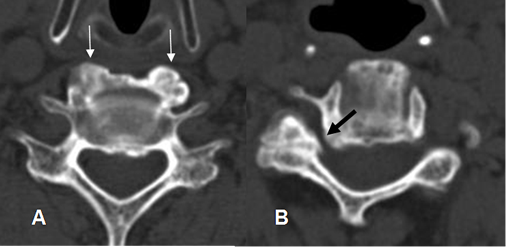

Fig 13. Artropatía degenerativa.

A y B: TAC cervical axial. Osteofitos anteriores e hipertrofia de articulación intervertebral derecha, que disminuye la amplitud del agujero de conjunción. (Flecha negra).